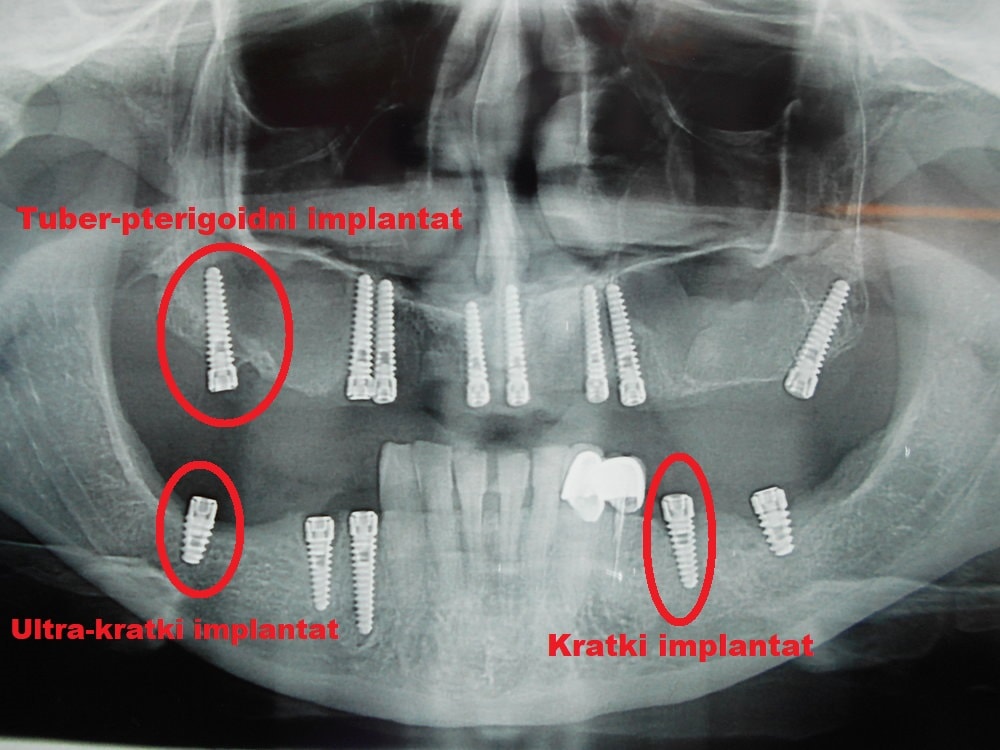

Oral implantology refers to surgical procedures aimed at functional rehabilitation of patients using dental implants, i.e., metal elements surgically implanted into the upper and lower jaw. Implants come in various forms and can be implanted in different positions and by different techniques. Currently, most implants are made of titanium.